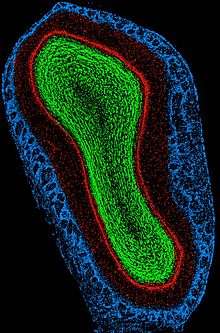

Blue - Glomerular layer;

Red - External Plexiform and Mitral cell layer;

Green - Internal Plexiform and Granule cell layer.

Top of image is dorsal aspect, right of image is lateral aspect. Scale, ventral to dorsal, is approximately 2mm.